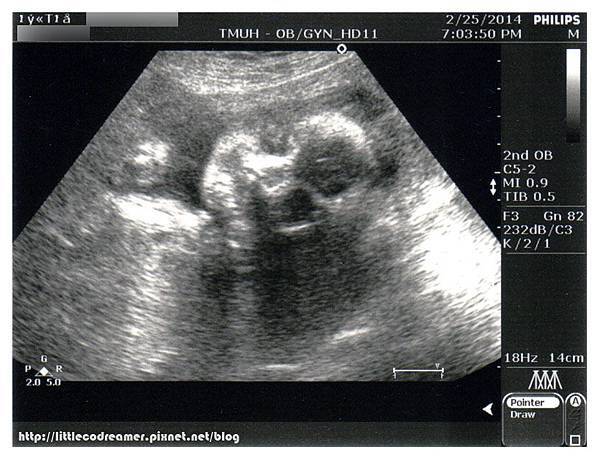

為了節省待在醫院的時間,等待抽血的空檔進行超音波檢查。這一次超音波是孕期中健保唯一給付。原本應該在第20週照,但當時安排了高層次超音波,所以就擺到24週產檢再使用。

健保給付超音波屬於標準檢查,看得細節比平時產檢自費照的還要多,花費的時間也比較久。檢驗師知道我的週數第一句話便問:「糖水喝完沒?幾分喝完的?」因為她要協助我控制時間,好讓我來得及抽血。北醫婦產科門診在二樓,抽血檢驗區在一樓,檢驗師貼心到連我走去的腳程都算在裡面。

小CO一切生長指數都正常,羊水量、胎盤、子宮頸長度也都正常。雖然胎位還沒轉正,但30週前都還會再轉。這一次檢驗師印給醫生看的照片有十多張,送了我二張。

↑這是孕期產檢超音波照中難得的露臉照。因為之後不是手擋、腳丫擋,就是乾脆背對著不給看。

↑雖然是給我二張,感覺好像只是角度相同,遠近不同而已。